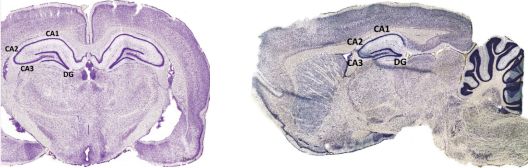

在详细解读这篇文章之前,我们首先来认识一下大脑中一个与记忆和神经元新生有关的脑区,即海马。该脑区因形似海马,故得名。海马包含有四个亚区,即CA1、CA2、CA3和齿状回(dentate,DG)(图4)。

海马主要负责学习和记忆。除此之外,在成年哺乳动物的大脑中,海马还具有另一个与众不同又很重要的特征,它可以为大脑提供新的神经元,这个过程也被称为“成年海马神经形成(adult hippocampal neurogenesis,AHN)”。目前发现的新生神经元主要来自于DG区。对大量的AD患者大脑的研究表明,海马DG区的神经形成显著改变。

图4 大鼠脑中海马的主要结构。左边为冠状面,右边为矢状面。图片来源:George Paxinos & Charles Watson,《The Rat Brain》(《大鼠脑立体定位图谱》第六版)